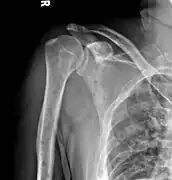

-

Skull X-ray showing multiple lucencies due to multiple myeloma -

Bone pain affects almost 70% of people with multiple myeloma and is the most common symptom.[16] Myeloma bone pain usually involves the spine and ribs, and worsens with activity. Persistent, localized pain may indicate a pathological bone fracture. Involvement of the vertebrae may lead to spinal cord compression or kyphosis. Myeloma bone disease is due to the overexpression of receptor activator for nuclear factor κ B ligand (RANKL) by bone marrow stroma. RANKL activates osteoclasts, which resorb bone. The resultant bone lesions are lytic (cause breakdown) in nature, and are best seen in plain radiographs, which may show "punched-out" resorptive lesions (including the "raindrop" appearance of the skull on radiography). The breakdown of bone also leads to the release of calcium ions into the blood, leading to hypercalcemia and its associated symptoms.

The diagnostic examination of a person with suspected multiple myeloma typically includes a skeletal survey. This is a series of X-rays of the skull, axial skeleton, and proximal long bones. Myeloma activity sometimes appears as "lytic lesions" (with local disappearance of normal bone due to resorption). And on the skull X-ray as "punched-out lesions" (pepper-pot skull). Lesions may also be sclerotic, which is seen as radiodense.[48] Overall, the radiodensity of myeloma is between −30 and 120 Hounsfield units (HU).[49] Magnetic resonance imaging is more sensitive than simple X-rays in the detection of lytic lesions, and may supersede a skeletal survey, especially when vertebral disease is suspected. Occasionally, a CT scan is performed to measure the size of soft-tissue plasmacytomas. Bone scans are typically not of any additional value in the workup of people with myeloma (no new bone formation; lytic lesions not well visualized on bone scan).